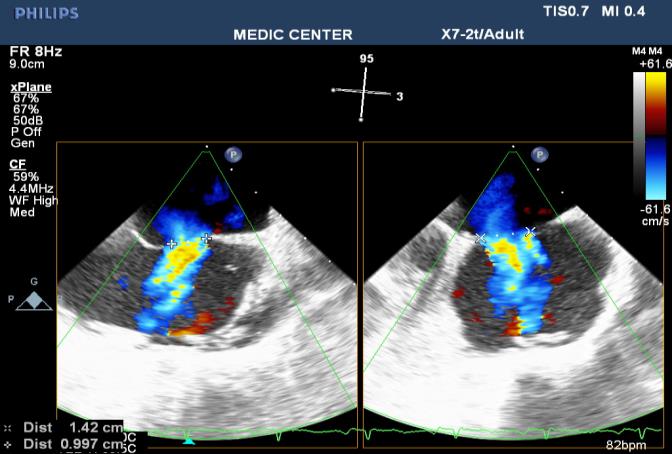

The X-plan mode can be used to estimate the maximal diameter of defect in two orthogonal planes. Three-dimensional (3D) TEE imaging is an important adjunct to 2D imaging because multiplanar reconstruction ensures that the defect is measured accurately.

Three-dimensional (3D) TEE images can be rotated to demonstrate the defect from the RA or LA side in evaluating the secundum atrial septal defect rims. This improves understanding of their shape and relationships to surrounding intracardiac structures.

Figure 24. 2DTEE X-plane showing the L-R shunting through the secumdum ASD

Figure 25. 3D image better demonstrates the shape and size of the secundum ASD

Figure 26. L-R shunting secundum ASD demonstrated with color flow imaging